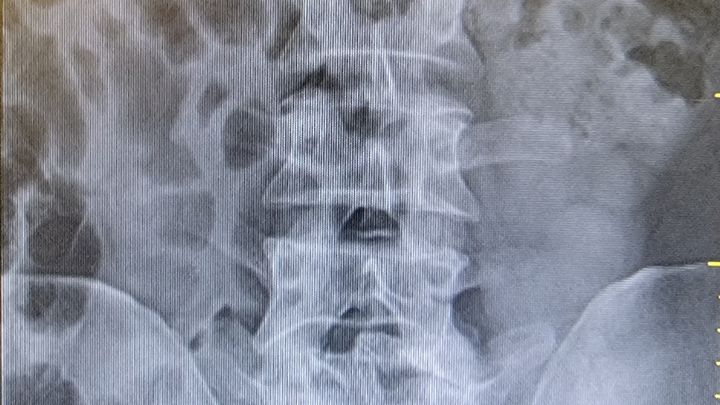

Hi, my name is Jason Robinson. I am 45 year old married father of 2 outstanding young men. I have worked as a maintenance person for 19 years on one property at a certain point it turned into my extended family. Around 8 years ago or so I started having trouble with me back. I would go to the doctor and would be told it was sprained given pills and sent on my way. Apx 3 years ago the pain started to get more frequent, and worse. Last year a doctor took an xray and they found the issues. I have a slipped disc a fractured vertebra and a misaligned spine. Because I didn't file L&I I can't claim it now. I have since been demoted from my job sent to another property and lost almost 1/4 of my hourly pay. My wife is a teachers aide, shes the strongest bravest women (beside my mother) I've ever known, but doesnt make a lot of money. Neither of us has family to count on, my mother and her father passed away years ago and we are estranged from our other parents. I would like the funds for rent as I won't be paid during recovery. For up to 12 weeks. I hope I can be deserving of some help as I don't have anywhere else to turn. Thanks Jason Robinson